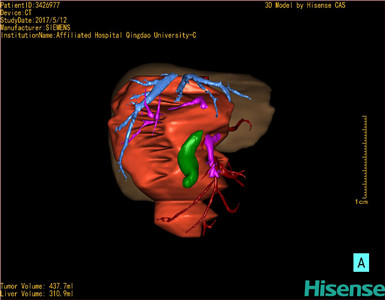

CT结果输入海信CAS系统后行3D重建及手术规划后,肿瘤位于右肾上腺区并周围淋巴结肿大,与血管关系紧密,建议化疗,静脉高营养、全量补液及对症支持治疗,患儿恢复良好,伤口无渗血渗液,无红肿疼痛,于2017-5-16出院。

术前三维重建:

重建图片